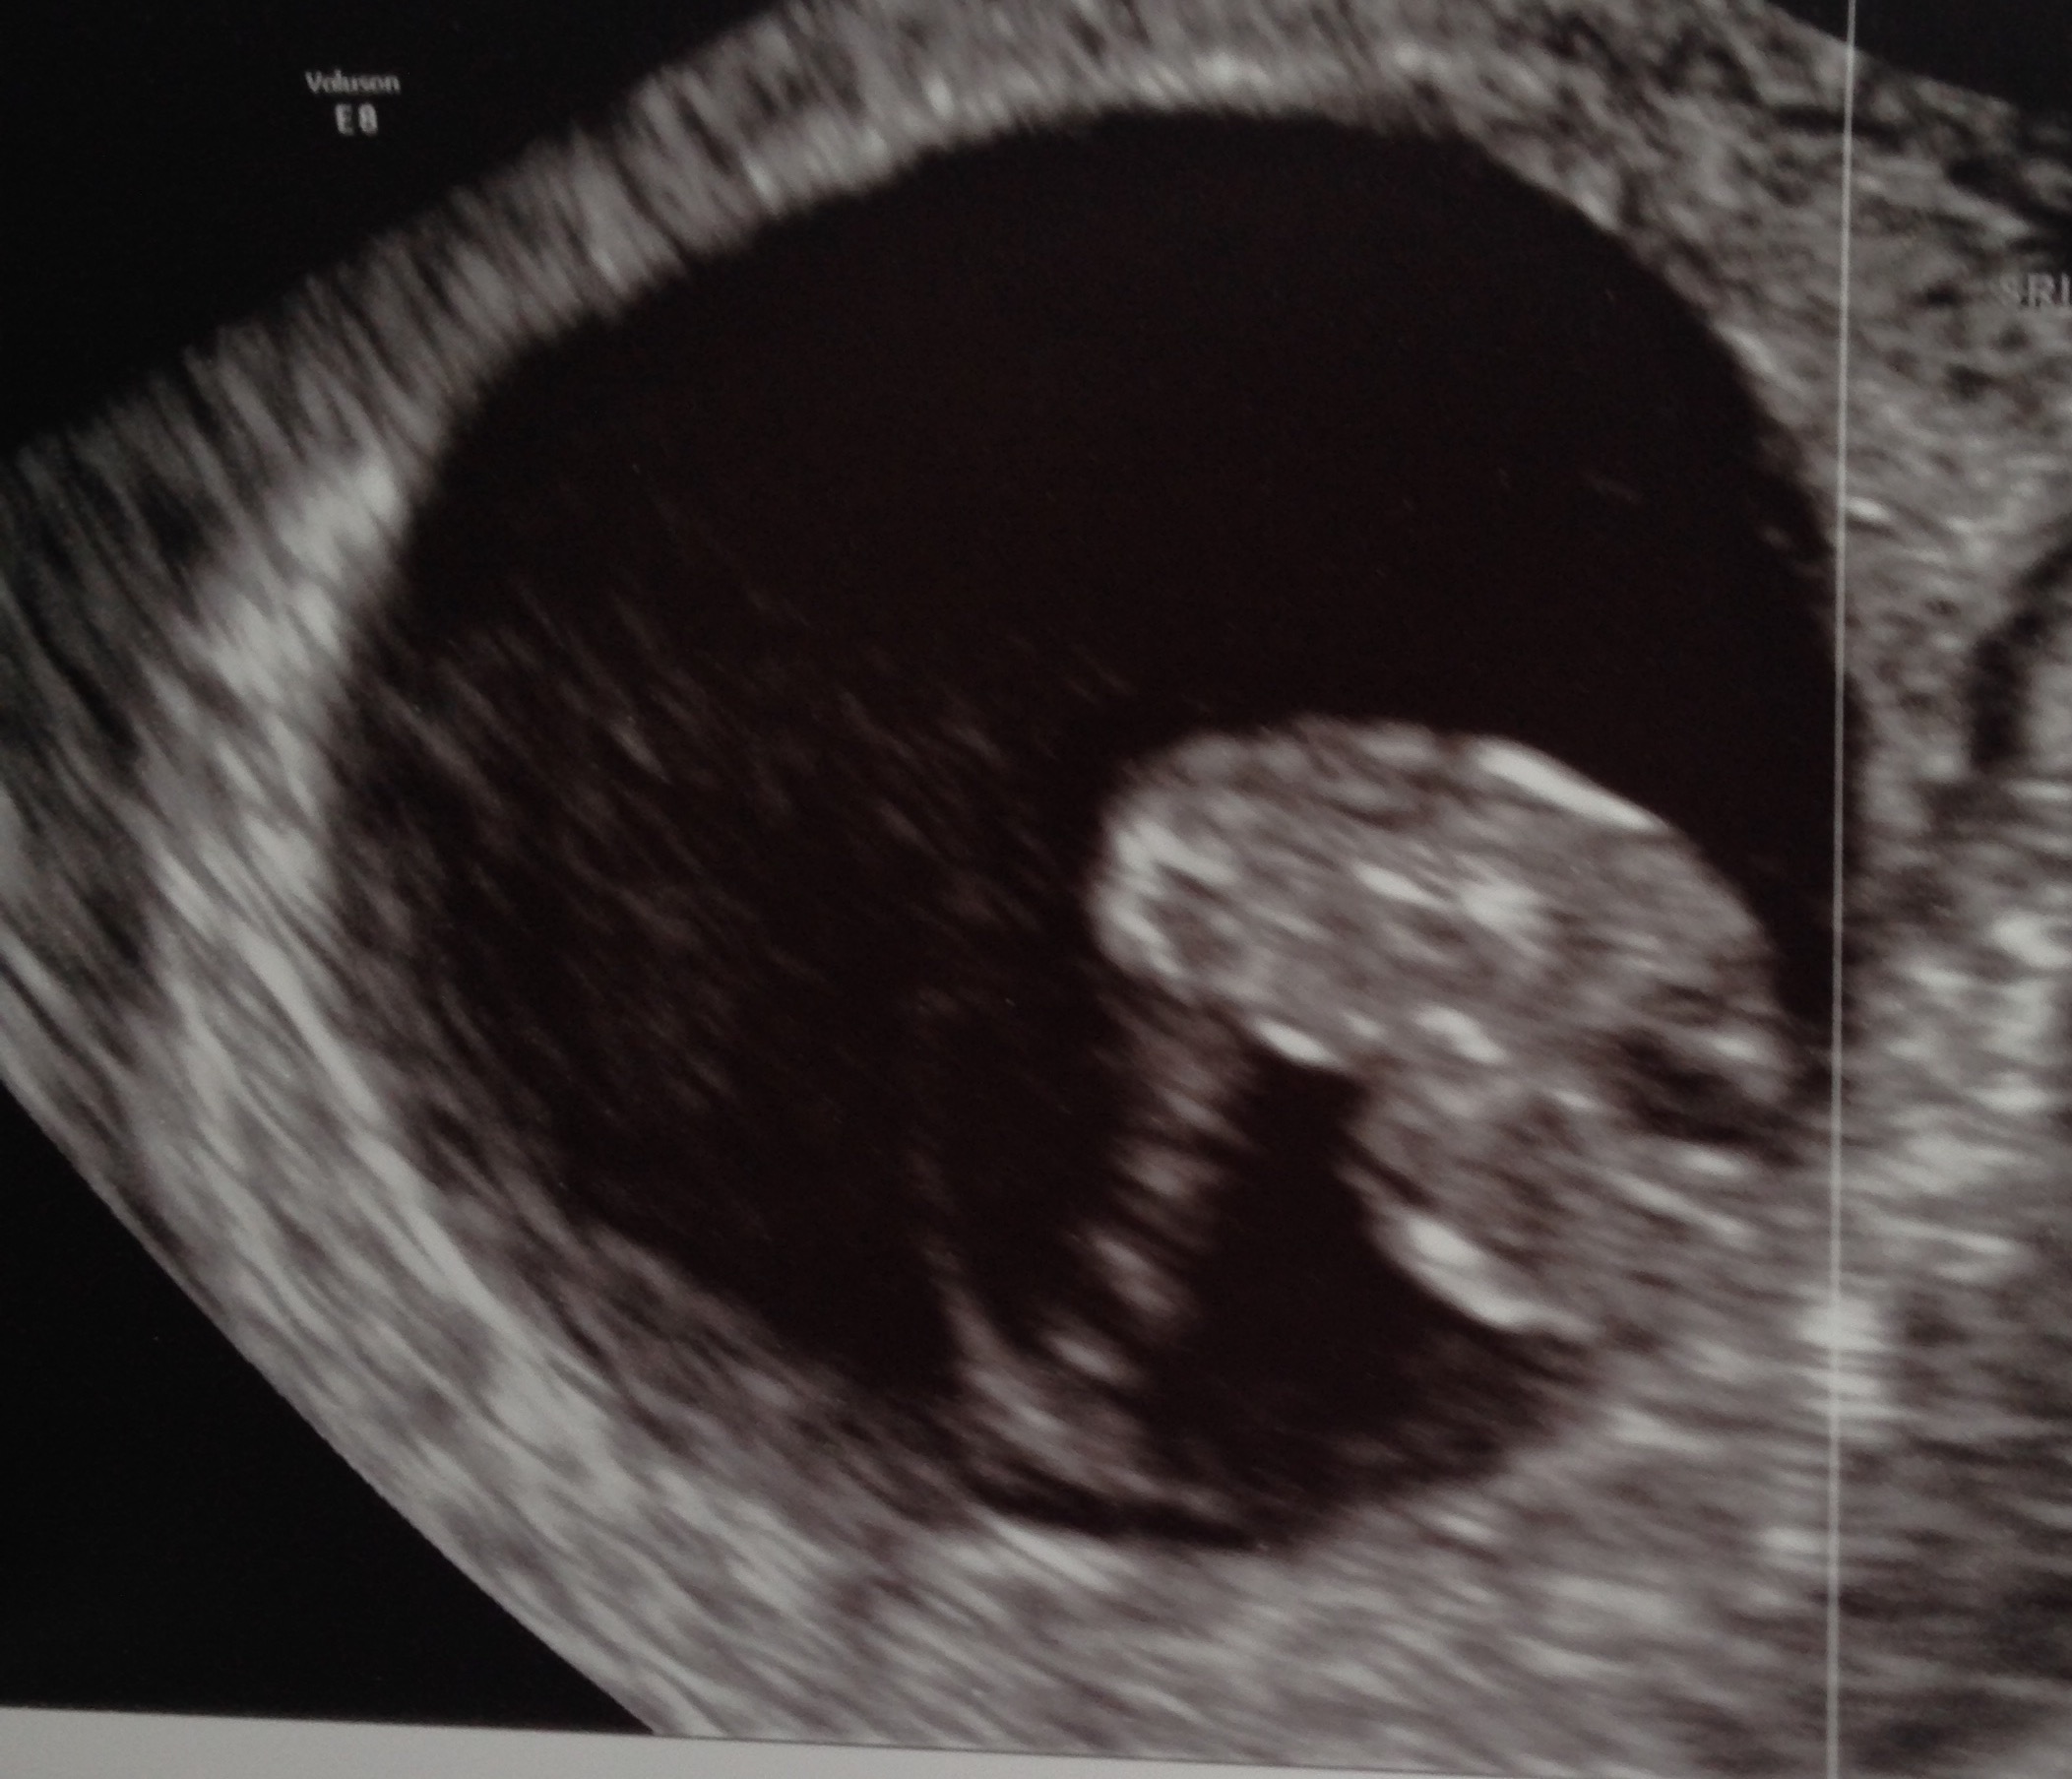

Hi all! This thread is magic! Love seeing everyone's precious little beans. Had my second scan today at 7+0 (last was at 5+6). Will post both in case ladies want to see progression (I know I like seeing that) . Got to hear the hb (133bpm) and smile cried so hard my cheeks hurt. Next US is next Friday and I may be released to a normal OB then.